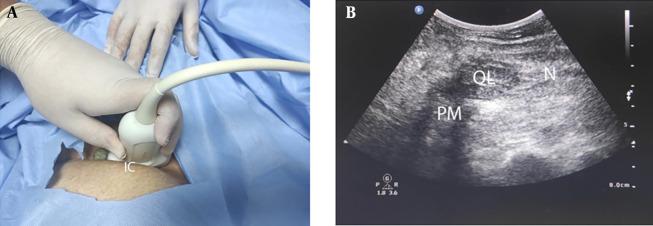

This randomized, controlled, single-blind trial involved 60 women presenting for CS under spinal anesthesia. The patients were assigned randomly to either the QLB type III, QLB type II, or lateral TAPB group. All blocks were performed using 20 mL of bupivacaine 0.25% bilaterally at the end of the operation with ultrasound guidance. Pain was assessed using the numerical rating scale (NRS) score at the post-anesthesia care unit (PACU) at 2, 4, 6, 8, 12, 18, and 24 hours. The level of patient satisfaction was graded on a 5-point Likert scale.

本随机、对照、单盲试验纳入了60例接受腰麻下行剖宫产手术的女性患者。患者被随机分配至III型QLB组、II型QLB组或外侧TAPB组。所有阻滞均在手术结束时于超声引导下双侧使用20 mL 0.25%布比卡因进行。在麻醉后恢复室(PACU)于术后2、4、6、8、12、18和24小时使用数字评分量表(NRS)评估疼痛。患者满意度采用5级李克特量表进行评分。